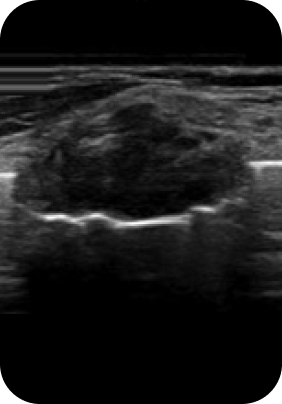

맘모톰, 비후성/알레르기 비염, 비중격 만곡증, 비밸브 협착증 등

질환에 따라 3DCT, 내시경 검사, 고해상도 초음파를 통해 정밀진단 후

정확한 증상에 따라 보험 실비 청구가 가능합니다.

대학병원급 검사 장비

유방외과 전문의 / 이비인후과 전문의

디에이성형외과에서는 대학병원급 검사 장비 시스템

각 분과의 전문의와 성형외과 전문의가 협진하여